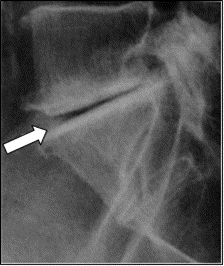

Którą patologię uwidoczniono na zamieszczonym rentgenogramie?

A. Złamanie nasady dalszej kości ramiennej.

B. Złamanie obojczyka.

C. Zwichnięcie kości ramiennej.

D. Stłuczenie łopatki.